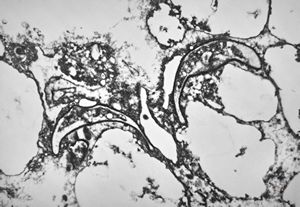

M,50y. | Pneumocystis carinii - lung